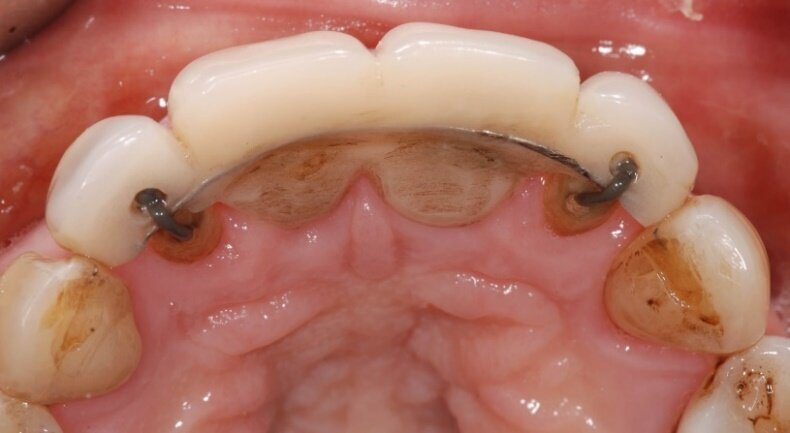

L’odontoiatra, valutate le aspettative della paziente, stila in data 25 ottobre 2010, un preventivo relativo a un protesi fissa supportata da due impianti, da 1.2 a 2.2, proponendo, in via preliminare, l’estrusione dei denti con un sistema invisibile e confortevole per mezzo dello stesso provvisorio (Fig. 6).

Per ottenere la trazione dei due incisivi laterali, la protesi provvisoria verrebbe sostenuta dai due incisivi centrali. A estrusione ottenuta si sarebbero estratti i due incisivi laterali ed inseriti contestualmente i due impianti nelle stesse sedi alveolari17.

Dopo alcuni mesi, la protesi provvisoria sarebbe stata sostituita, collocando i monconi (abutments) sui due impianti già inseriti (1.2 e 2.2). Con la medesima tecnica, sarebbero poi stati estrusi i due incisivi centrali. Ottenuta la maturazione dei tessuti molli e un livello gengivale desiderato, si sarebbero estratti anche i due incisivi centrali e intrapresa la fase protesica definitiva.

Tutto ciò viene dettagliatamente spiegato sia verbalmente, sia descritto nel “Consenso informato” che la paziente sottoscrive dopo aver richiesto un secondo consulto presso un altro studio. Il trattamento estrusivo dei due incisivi laterali inizia nel gennaio 2011 (Figg. 7, 8). Al raggiungimento del risultato desiderato (Figg. 9, 10), si attendono 60 giorni di “stabilizzazione” dell’osso alveolare18 (Figg. 11, 12).